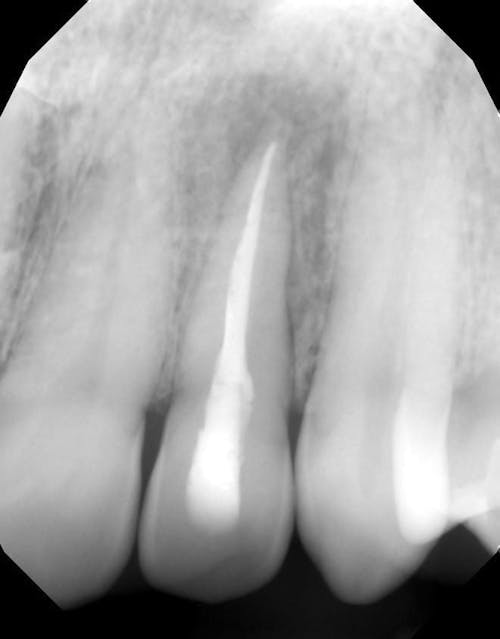

So, what is a root canal? When a damaged, chipped or diseased tooth—or teeth—causes pain, discomfort, or sensitivity, which cannot be reversed by other means, a root canal is often the best treatment. Essentially, a root canal removes and deactivates the nerve endings—or pain receptors—reversing your ability to feel pain in those teeth. This process saves your natural tooth while eradicating the pain.